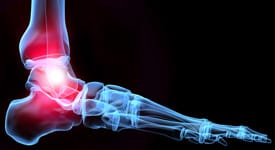

Pé de Charcot é uma condição crônica do pé que se encontra em condições que provocam a perda de sensação no pé, mais comumente a diabetes. Como resultado da perda de sensibilidade, o pé é incapaz de manter a sua estrutura normal, e os ossos do pé e tornozelo entram em colapso (desmoronando). O resultado é a dor e inflamação. Com o tempo, os ossos e articulações do tornozelo pode ser danificados, e levados a dor crônica e úlceras nos pés.